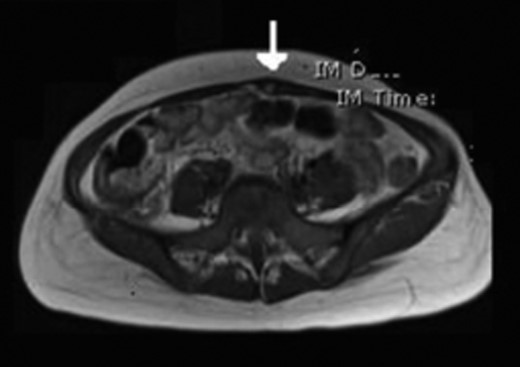

A 32-year-old lady was referred to our clinic with complaints of a painful lower abdominal lump. It had been present for 4 months and had become more symptomatic over time. She had a past medical history of hyperthyroidism but nothing else of note. Abdominal examination revealed a 2-cm infra-umbilical palpable lump within the left rectus muscle which was mildly tender and did not have a cough impulse. An ultrasound scan showed a hard 2 × 3 cm lesion in her left rectus and no evidence of a hernia (Fig. 1). To characterize the lesion further, an magnetic resonance imaging (MRI) scan was organized and it revealed a benign lesion consistent with an intramuscular lipoma (Fig. 2). She was taken to the theatre for excision of the lump. Intra-operatively she was found to have an inflammatory mass and therefore a wide excision was carried out. The patient was discharged with no complications. Histological examination revealed endometriosis of the abdominal wall. She has been followed for 6 months with no signs of a recurrence.

MRI showing a benign lesion consistent with an intramuscular lipoma.